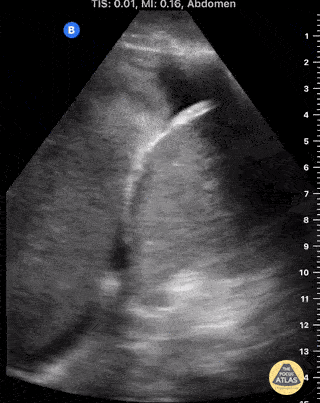

Male ICU patient developed respiratory failure and opacified L hemithorax day 2 post-op from TEVAR for Type B aortic dissection. Longitudinal view from L posterior axillary line showed hemothorax with a large intrapleural blood clot and small medial sliver of atelectatic lung. Paradoxical movement with inspiration and absence of air bronchograms assist in distinguishing clot from lung parenchyma. Samuel Eglin, MD